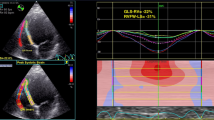

Regarding the intraobserver reproducibility, the ICC was 0.903 (95% CI 0.677–0.974) for FLC and 0.961 (95% CI 0.861–0.990) for FTC. The time required to measure these parameters was 67.1 ± 15 s for operator A. Regarding interobserver reproducibility, the ICC was 0.819 (95% CI 0.453–0.951) for FLC and 0.894 (95% CI 0.653–0.972) for FTC. The time required to measure these parameters was 168 ± 28 s for operator B. Representative cases are shown in Fig. 5.

Representative cases. The straight red lines indicate the measured locations for RVLd, RVLs, RVDd, and RVDs. The polygonal lines indicate the endocardium of the RV at end-diastole and end-systole. (a, b) Four-chamber cine CMR of a woman in her 40 s; (a) end-diastole; (b) end-systole. CMR revealed no morphological abnormalities in the RV. (c, d) A woman in her 40 s with a history of ventricular tachycardia. CMR revealed an atrial septal defect and a left-to-right shunt (c, arrow). The Qp/Qs ratio was estimated at 2.2 by the phase-contrast method. (e, f) A man in his 70 s with right heart failure. Thickened pericardium is visible (e, arrow). (g, h) A man in his 40 s with a history of ventricular tachycardia. Remarkable impairment of RV contraction, and bulging and fat infiltration of the RV (g, arrow) are visible. RVLd Right ventricular length at end-diastole, RVLs Right ventricular length at end-systole, RVDd Right ventricular diameter at end-diastole, RVDs Right ventricular diameter at end-systole, CMR Cardiac magnetic resonance imaging.